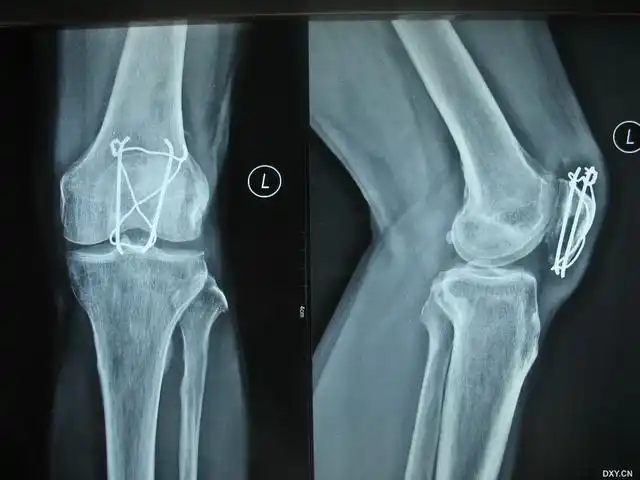

54岁髌骨粉碎性骨折髌骨爪克氏针联合内固定手术一例

65岁髌骨骨折髌骨爪克氏针联合内固定手术一例